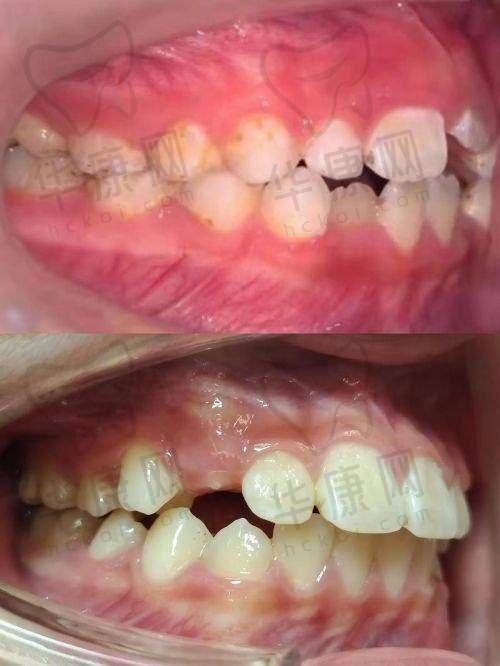

曾经有一位小朋友,牙齿存在明显的地包天问题,家长非常担心会影响孩子的面部发育和自信心。来到株洲荷塘唯美口腔后,医生为他进行了详细的检查和评估,制定了个性化的早期矫正方案。在矫正过程中,医生和护士给予了孩子充分的关心和鼓励,让孩子能够积极配合治疗。经过一段时间的矫正,孩子的地包天问题得到了明显改善,面部外观也更加美观。家长对矫正成效非常满意,也对医院的专精服务和技术水平赞不绝口。